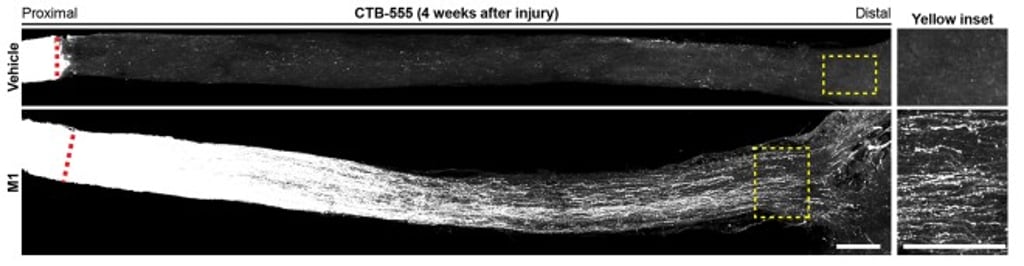

“M1 treatment sustains long-distance axon regeneration from the optic chiasm, i.e. midway between the eyes and target brain region, to multiple subcortical visual targets in the brain. Regenerated axons elicit neural activities in target brain regions and restore visual functions after M1 treatment. Our study highlights the potential of a readily available and non-viral therapy for CNS repair.”

“This time we have used the small molecule M1 for repairing CNS simply by intravitreal injection into the eyes, which is an established medical procedure for patients, i.e., for macular degeneration treatment. Successful restoration of the visual function such as pupillary light reflex and responses to looming visual stimuli, e.g. visually induced innate defensive responses to avoid predators, was observed only in M1-treated mice four to six weeks after the optic nerve had been damaged,” said Dr Au Ngan-pan, Research Associate in the Department of Neuroscience.